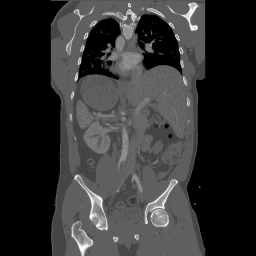

Augmented Surgery

Communication / Telemedicine